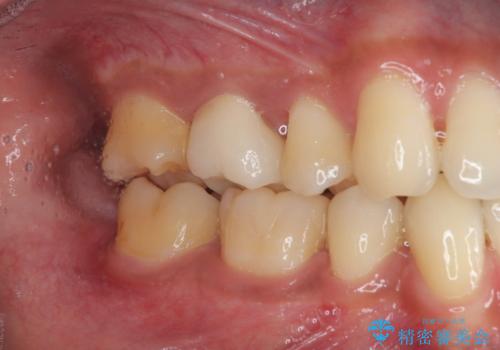

- 銀歯をセラミックにしたいとのことで来院された患者様です。検査の結果、メタルインレーが大きくご自身の歯の残る量を考慮して、オールセラミッククラウンによる補綴治療を行っていくことにしました。

拡大鏡視野下で、メタルインレー、虫歯の除去を行いオールセラミッククラウンに適した形に整えました。

歯と歯茎の間に圧排糸と言われる糸を入れてシリコーン印象材にて型どりをしました。